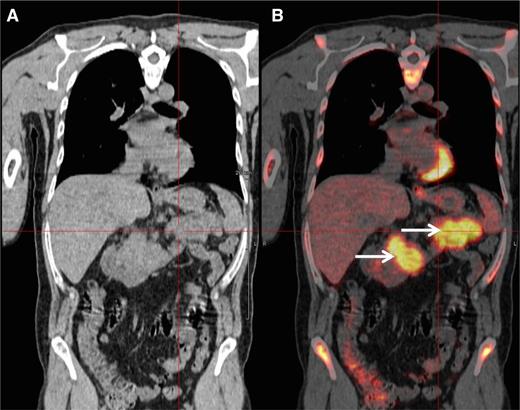

A 48-year-old man was diagnosed with IgG-κ myeloma in 2013. The patient presented with myeloma-related anemia and bone lesions. The prognostic analysis did not show the presence of high-risk FISH abnormalities, but a stage 3 ISS and an elevated LDH level. At this time no extramedullary disease was detected using PET-CT and MRI. The patient received induction therapy (3 courses of bortezomib-lenalidomide-dexamethasone), intensification (high-dose melphalan/ASCT), consolidation (2 courses bortezomib-lenalidomide-dexamethasone), and lenalidomide maintenance (IFM/DFCI2009 clinical trial). After completion of this sequence, the patient achieved a stringent CR (sCR). During cycle 10 of the maintenance therapy, the patient presented with epigastric abdominal pain and vomiting. Biochemistry tests showed elevated lipase levels, and a CT scan revealed a homogeneous hypertrophy of the pancreas. At the same time, the patient did not display any clinical criteria of myeloma relapse: he had normal blood cell counts and no CRAB symptoms. The bone marrow aspirate did not show abnormal plasmacytosis, and there was no M-spike in the serum electrophoresis. However, serum and urine κ free light-chain levels were elevated (250 mg/L and 300 mg/24 hours, respectively) confirming a light-chain escape. A PET-CT scan revealed an intense fluorodeoxyglucose (FDG) avidity of the pancreas (maximum standard uptake value = 11; Figure 2). The biopsy of the pancreas confirmed the infiltration by clonal PCs. Genetic and molecular analyses were performed and revealed no 17p deletion, no 14q32 recurrent translocation, and no BRAF mutation. The patient started pomalidomide-cyclophosphamide-dexamethasone therapy and achieved a CR according to standard criteria, including PET-CT. After 6 cycles, the patient is still continuing therapy.

PET-CT scan. PET-CT scan (A) demonstrating increased FDG avidity of the pancreas (B, arrows) in an MM patient who developed epigastric pain during maintenance therapy.

The present case illustrates the diagnostic and therapeutic approach to an EMM relapse. This high-risk MM patient (stage 3 ISS, elevated LDH) achieved an sCR after the completion of an intensive approach combining lenalidomide-bortezomib–based induction and consolidation, high-dose melphalan, and lenalidomide maintenance. During maintenance, he presented with abdominal symptoms that did not initially suggest an MM relapse. However, clinical tests revealed a pancreatic tumor, which should in this context be considered as a possible extramedullary manifestation. Moreover, in the present case, the hypothesis of extramedullary disease was supported by the light-chain escape, which could be a feature of EMM relapse.25 This particular type of relapse strongly supports the international guidelines that recommend the routine inclusion of Bence Jones proteinuria in the follow-up of MM patients.46 In this context of probable EMM, a PET-CT scan is a valuable tool to detect lesions with increased FDG avidity.47 In our daily practice, PET-CT imaging is commonly used in case of (1) clinical suspicion of EMM, (2) light-chain escape, and (3) staging and follow-up of nonsecretory MM. Whenever possible, a biopsy should be performed to confirm the diagnosis of extramedullary disease. Extramedullary relapse has a dismal prognosis with an overall survival of <6 months.34 As is usual, the therapeutic strategy should take into account the previous lines of treatment and the duration of response. In the present case, we started a pomalidomide-based triplet combination. Pomalidomide has demonstrated a response rate of ∼30% in EMM relapse.18 However, novel approaches are warranted to improve response rates and overall survival. The efficacy of monoclonal antibodies (eg, daratumumab and elotuzumab) in EMM has not been reported so far. Importantly, the molecular characterization of PCs may help to guide therapy. Indeed, BRAF mutation is a rare molecular event in MM (∼3% of patients) but seems to be more frequent in EMM patients.48 Andrulis et al reported a durable response using the BRAF inhibitor vemurafenib in an EMM patient harboring the BRAF V600E mutation.48 Because of this potential therapeutic impact, we check the presence of BRAF mutations in tissue samples of all patients with EMM relapse. Similarly, Heuck et al recently reported promising clinical responses using the mitogen-activated protein kinase inhibitor trametinib in relapsed MM patients harboring RAS or RAF mutations.49 Recently, immune therapies using autologous T cells expressing a tumor-specific chimeric antigen receptor have also shown promising responses (including a complete response) in relapsed EMM patients.50,51 Finally, radiotherapy of a soft-tissue plasmacytoma should always be considered to improve local disease control and analgesia.